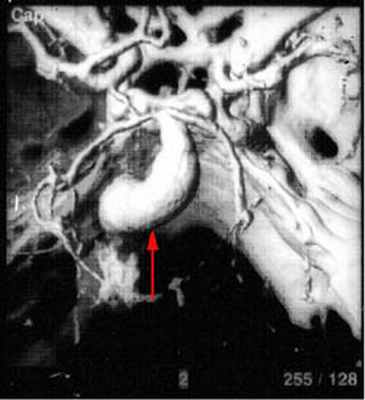

ЗD-KT ангиография - мешотчатая аневризма развилки основной артерии

3D-KT ангиография - фузиформное расширение основной артерии

4. Более 25 мм – гигантские.Велизиев круг (артериальный круг головного мозга) с гигантской аневризмой внутренней сонной артерии (слева

Велизиев круг (артериальный круг головного мозга) с гигантской аневризмой внутренней сонной артерии (слева)